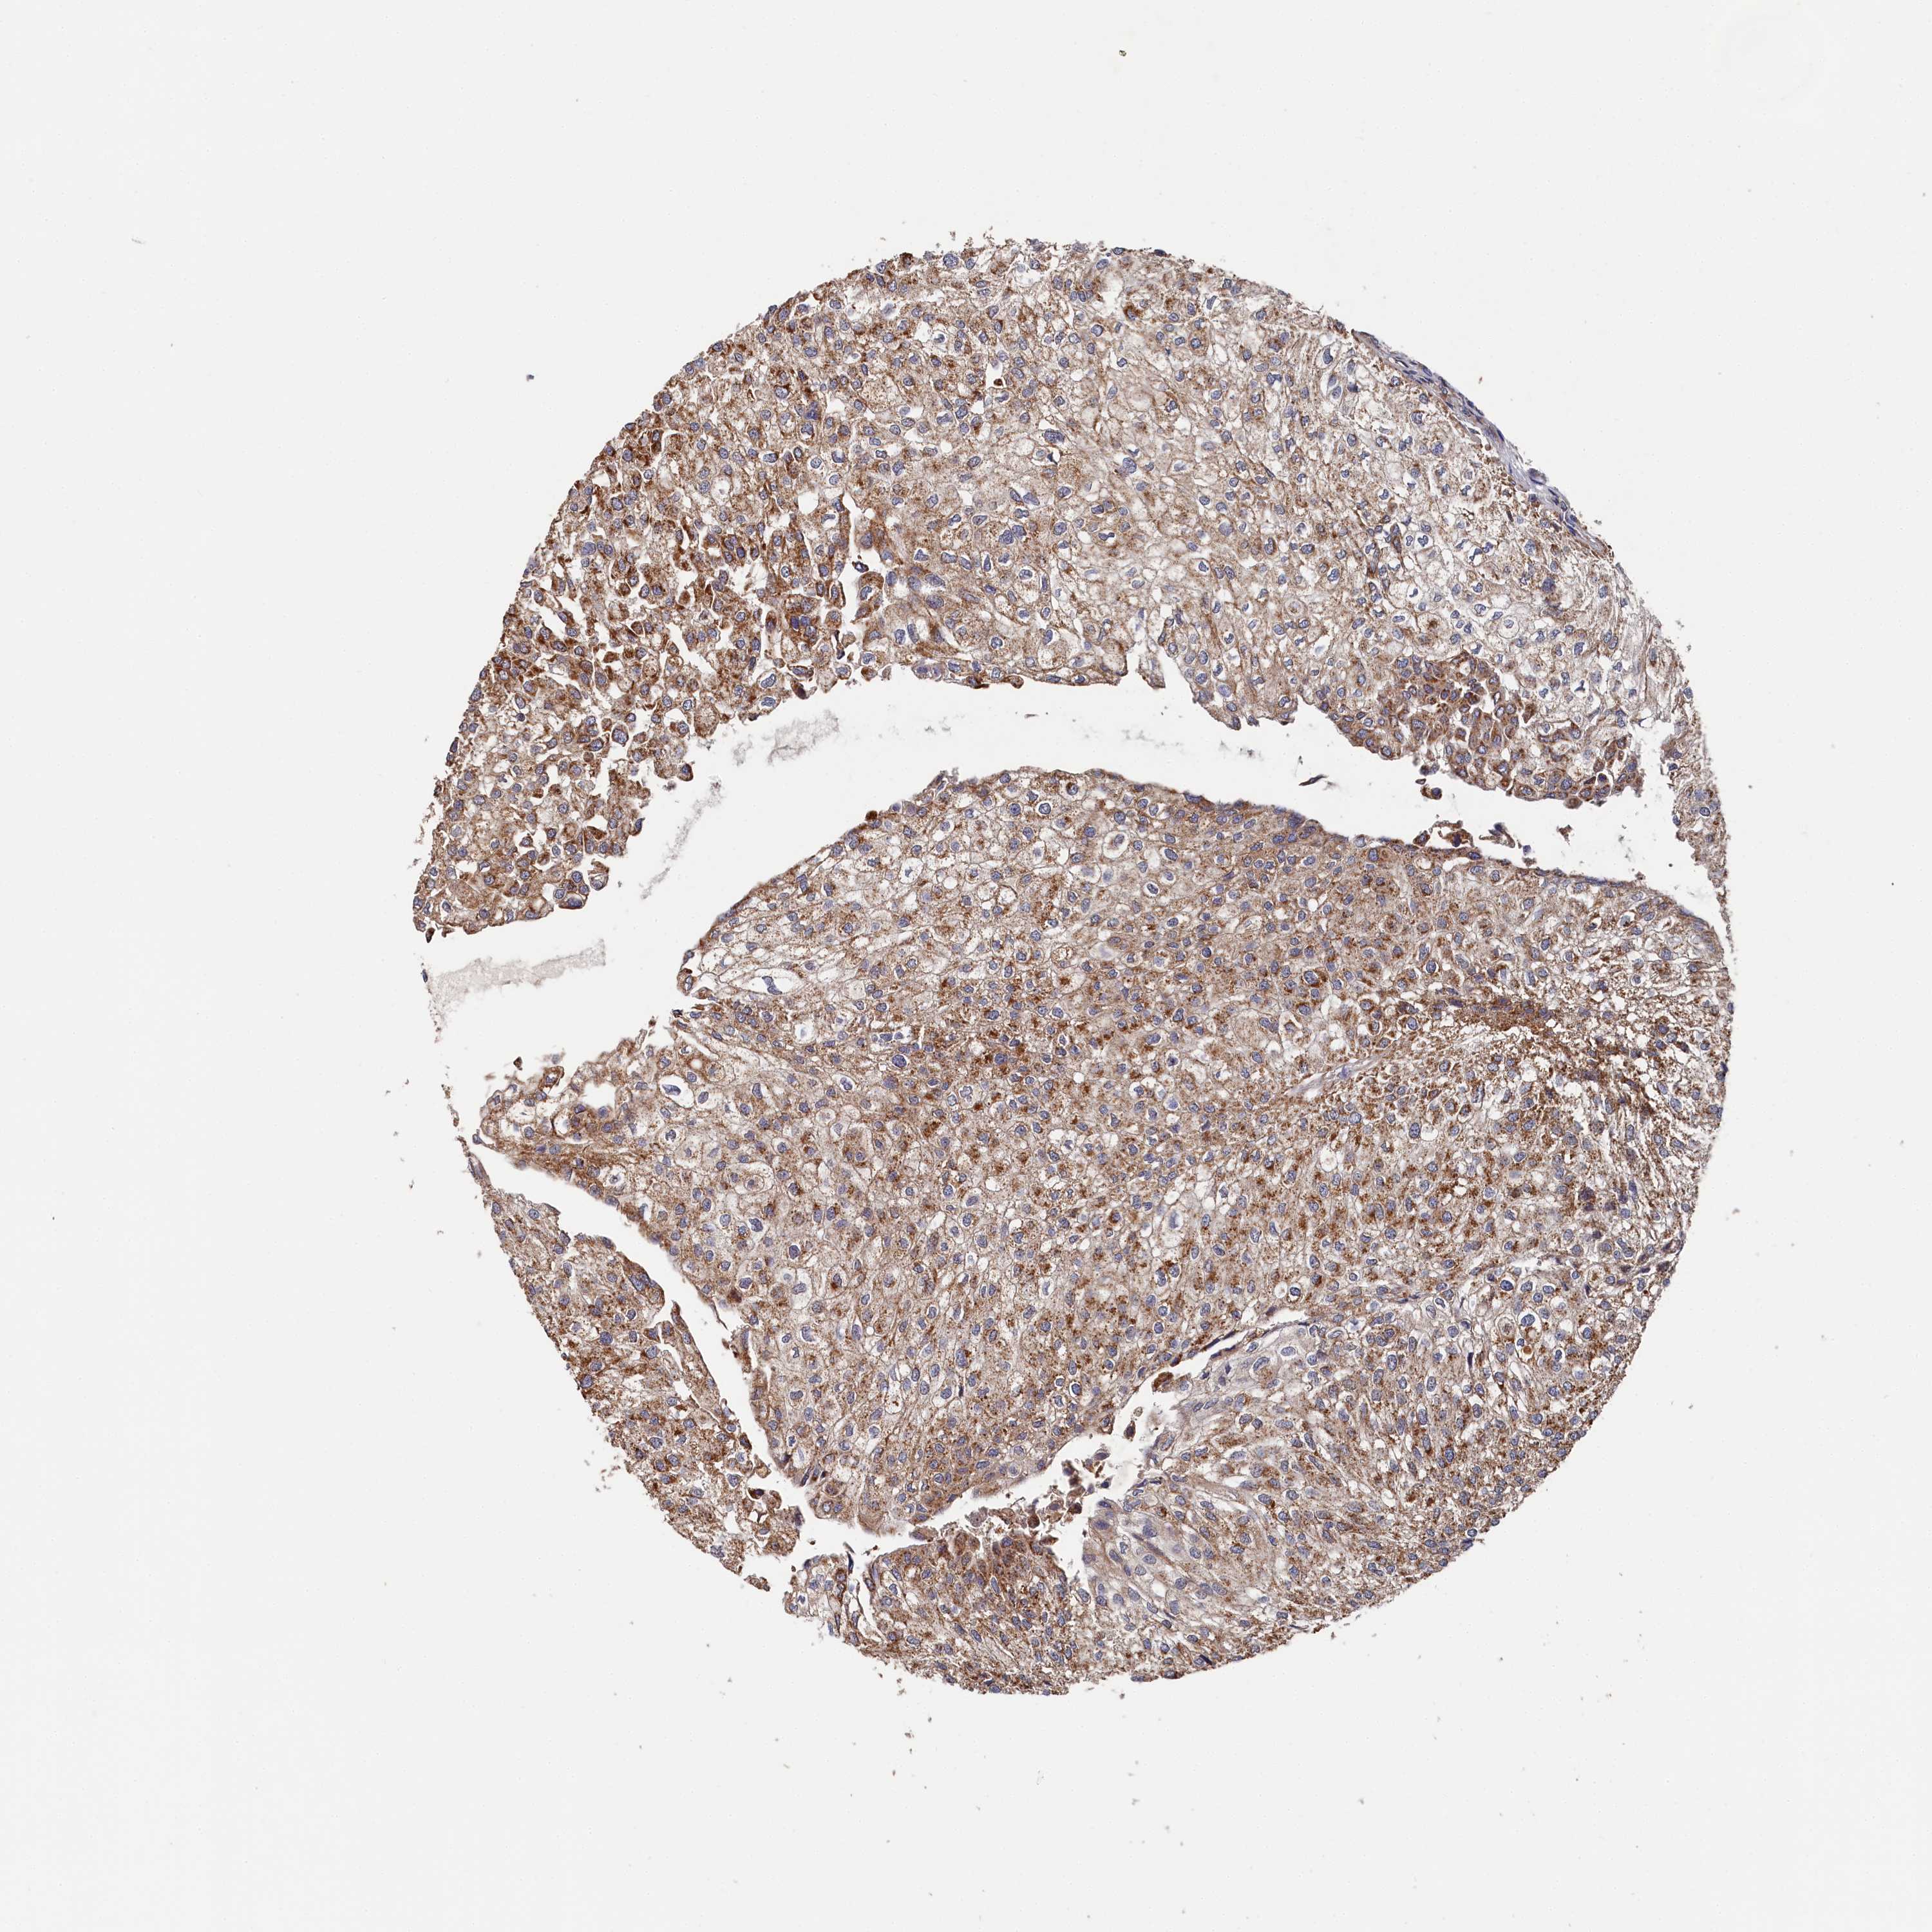

UROTHELIAL CANCER - Protein expressioni

A mouse-over function shows sample information and annotation data. Click on an image to view it in a full screen mode. Samples can be filtered based on level of antibody staining by selecting one or several of the following categories: high, medium, low and not detected. The assay and annotation is described here.

Antibody stainingi

Antibody staining in the annotated cell types in the current human tissue is reported as not detected, low, medium, or high, based on conventional immunohistochemistry profiling in selected tissues. This score is based on the combination of the staining intensity and fraction of stained cells.

Each image is clickable and will lead to virtual microscopy that enables deeper exploration of all samples and also displays staining intensity scores, fraction scores and subcellular localization as well as patient and tissue information for each sample.

Antibody HPA039965

Staining

High

Medium

Low

Not detected

Intensity

Strong

Moderate

Weak

Negative

Quantity

>75%

75%-25%

<25%

None

Location

Nuclear

Cytoplasmic/membranous

Cytoplasmic/membranous,nuclear

Urothelial carcinoma, High grade

Urothelial carcinoma, Low grade